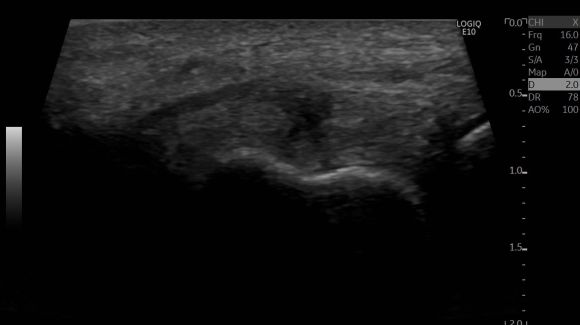

The patient had trouble for several months. Conservative treatment has not produced a positive effect. The patient comes for diagnostics and treatment. An ultrasound examination shows a tendinosis in the extensor tendon with Doppler grade 2. We did an ultrasound fenestration treatment with a 22 G needle in this case.

Elbow laterally outside